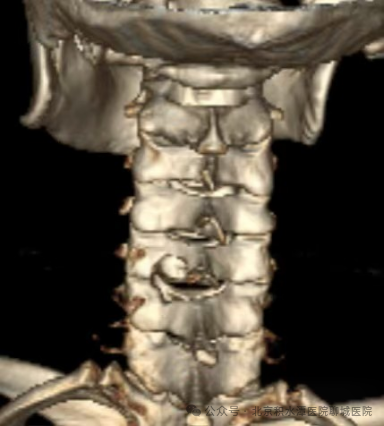

术后影像:去除C5/6左侧椎管背侧少量骨质

进行减压并摘除突出的间盘组织

术后影像:去除少量骨质扩大胸椎椎管

并取出骨化的黄韧带